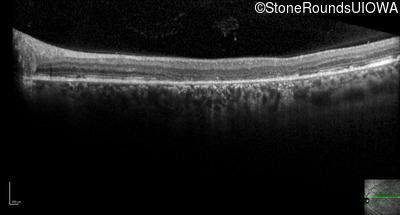

Optical Coherence Tomography - Right - 20/200

Exemplar / OCT Stack